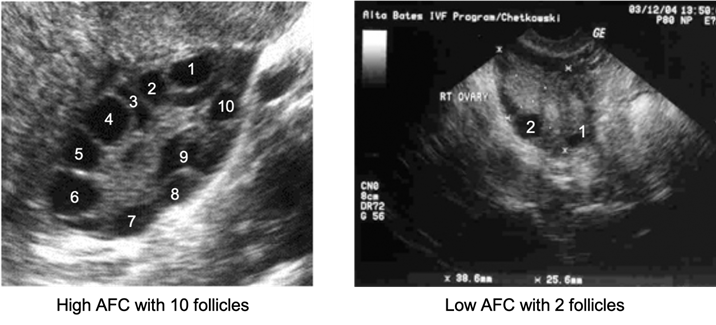

productions and egg maturation). Transvaginal ultrasound to asess

Basal Antral Follicle Count (BAFC-Number of antral follicles you have

is indicative of the number of eggs you could potentially retrieve)